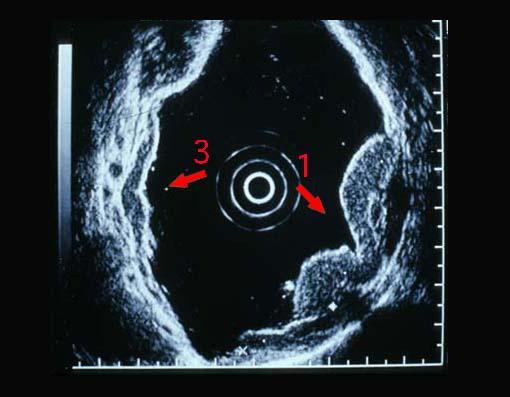

多発腫瘍を主体とした進行胃悪性リンパ腫のエコー像  ミニチアプローベ(miniature probe)を用いて、水浸法で検査された超音波内視鏡像です。層構造を保ちつつ、2~4層が肥厚しており、低エコー(hypoechoic)を示す隆起(矢印1と3の病変に相当)を形成しています。